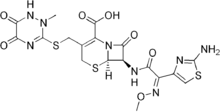

Antibiotique

Un traitement antibiotique empirique doit être entrepris sans délai, avant même d'avoir les résultats des examens complémentaires. Le choix de la molécule utilisée dépend de l'épidémiologie bactérienne locale des méningites. Par exemple, au Royaume-Uni, une céphalosporine de troisième génération telle que le céfotaxime ou la ceftriaxone est recommandée[26],[28]. Aux États-Unis, il est recommandé d'associer une céphalosporine de troisième génération et la vancomycine, en raison de résistance accrue de streptocoque aux céphalosporines[10],[9],[26]. Le chloramphénicol, seul ou associé à l'ampicilline, semble tout aussi efficace[50].

Un tel traitement peut être adapté en fonction de l'âge du patient et de la possibilité d'existence d'un brèche ostéoméningée (notion de traumatisme crânien ou d'intervention neurochirurgicale préalable)[10]. Chez les jeunes enfants, les sujets de plus de 50 ans, et les sujets immunodéprimés, il est recommandé l'addition d'ampicilline à une céphalosporine de troisième génération afin de couvrir Listeria monocytogenes[10],[26]. Lorsque le résultat de l'examen bactériologique direct est connu et qu'il permet d'orienter vers un germe particulier, il est possible de modifier l'antibiothérapie pour cibler le germe suspecté[10]. Le résultat de la culture du LCS est plus long à obtenir, avec en général un délai de 24 à 48 heures. Une fois connu, le traitement antibiotique peut être adapté au germe identifié et à son spectre de résistance[10]. Pour qu'un antibiotique soit actif au cours d'une méningite, il faut non seulement qu'il soit actif vis-à-vis du germe en cause, mais aussi qu'il diffuse dans le LCS en quantité suffisante. Cette diffusion dépend de la capacité intrinsèque de la molécule à passer la barrière hémato-encéphalique, qui varie d'une molécule à l'autre.

L'efficacité des principaux antibiotiques utilisés au cours de la méningite n'a pas été évaluée sur des sujets humains pour des raisons éthiques ; les données d'efficacité sont donc issues de tests sur des lapins de laboratoire[10]. La méningite tuberculeuse nécessite un traitement antibiotique prolongé pour une durée totale d'un an voire plus[14].